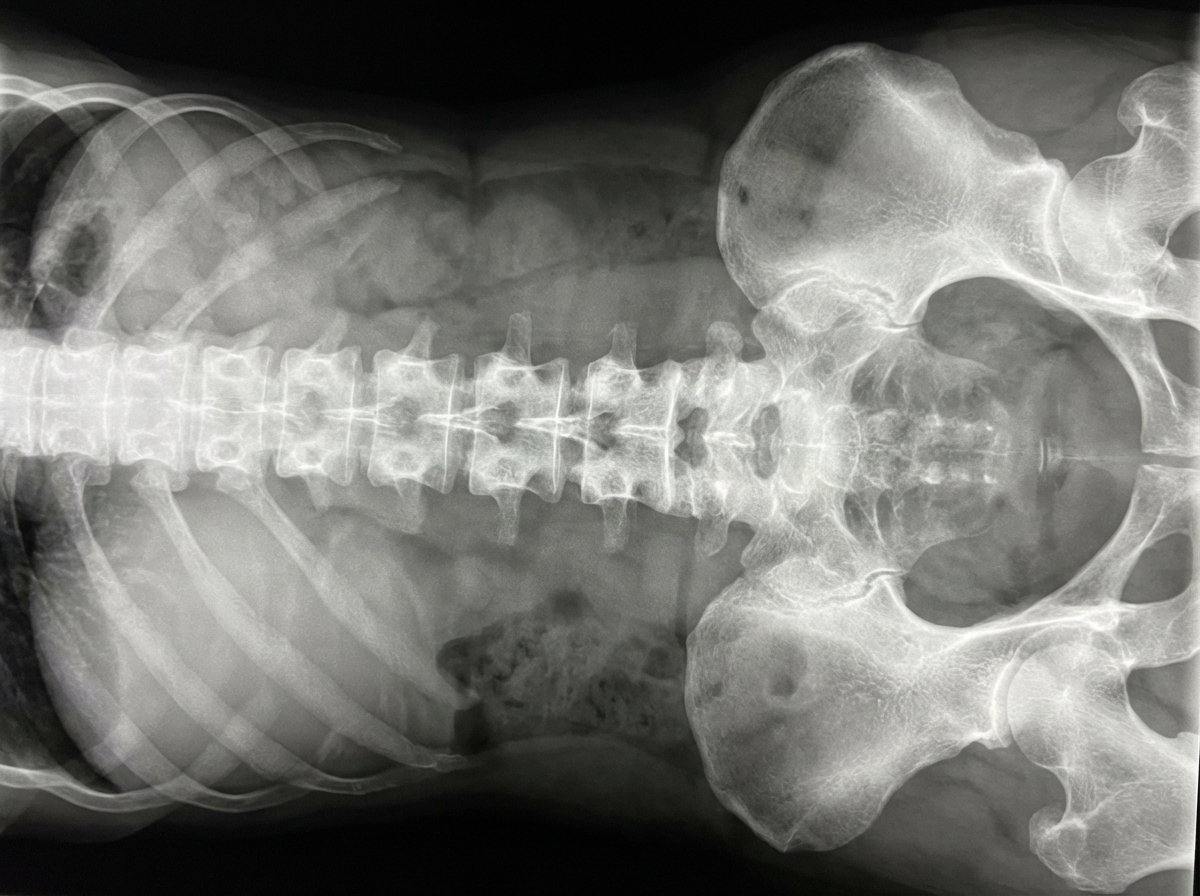

An X-ray of the right distal tibia and fibula is shown. What condition does it possibly represent?

Explanation: ***Osteosarcoma*** - Typically presents as a **mixed lytic-sclerotic lesion** in the **metaphyseal region** of long bones, commonly affecting the distal femur or proximal tibia - Classic radiographic features include **Codman's triangle** (periosteal elevation) and **sunburst pattern** (radiating spicules of bone) *Ewing's sarcoma* - Predominantly affects the **diaphyseal region** of long bones, not the metaphysis like osteosarcoma - Characteristic **onion-skin appearance** due to laminated periosteal reaction, distinct from osteosarcoma's sunburst pattern *Soft tissue tumor with fibular involvement* - Soft tissue tumors typically show **soft tissue mass** without primary bone destruction or formation - Would not demonstrate the **aggressive bone formation** and **sclerotic changes** typical of primary bone tumors *Osteoclastoma* - Also known as **giant cell tumor (GCT)**, typically occurs in the **epiphyseal region** of long bones - Presents as a **soap-bubble appearance** with well-defined lytic lesions, lacking the mixed sclerotic pattern of osteosarcoma